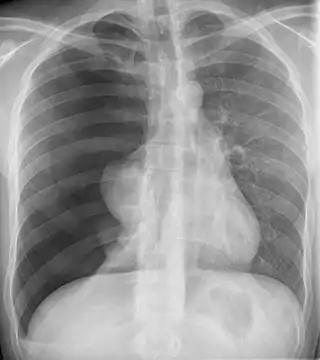

![]() Radiografía de un neumotórax. La amplia mayoría de los neumotórax catameniales ocurren en el lado derecho, al igual que en este caso. | ||

El neumotórax catamenial es un neumotórax espontáneo que recurre durante la menstruación, dentro de las 72 horas anteriores o posteriores al inicio de un ciclo. Es una de las manifestaciones clínicas de la endometriosis torácica. Se caracteriza por producirse, a las pocas horas o días de comenzar la menstruación, un neumotórax —acumulación de aire entre el pulmón y la serosa que lo rodea, la pleura—.[2] Aunque se asocia con la presencia de tejido endometrial en el tórax, no es un hallazgo histológico constante en las personas afectadas. Según la fuente, entre un 87.5 % y un 100 % de los casos ocurren en el pulmón derecho.[2] El tratamiento consiste en suprimir la secreción de estrógenos por parte del ovario, por ejemplo con anticonceptivos orales, o en cirugía de tórax.[3]